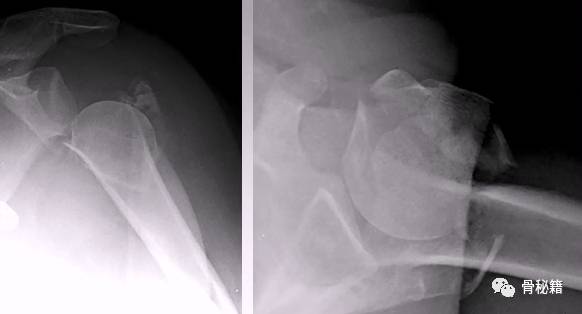

肱骨近端骨折十分常见,我们临床中最常用的入路为胸大肌-三角肌入路。

大结节向后侧移位较大,所以外侧劈三角肌入路 逐渐得到了大家的认可。